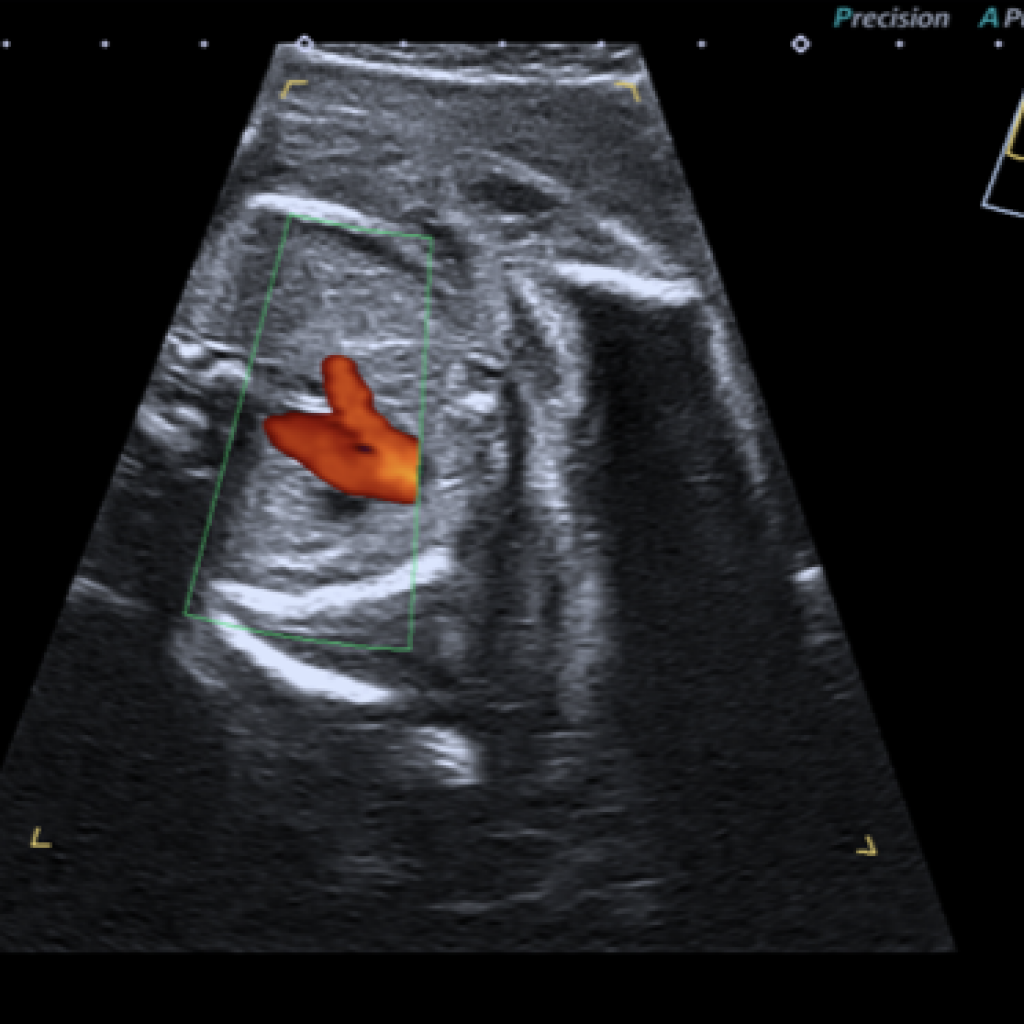

Comment je fais une echographie f tale Manipulation de la sonde et du f tus pour un examen plus precis ScienceDirect

Doppler f tal ce qu il faut savoir sur cet examen de la grossesse Femme Actuelle Le MAG